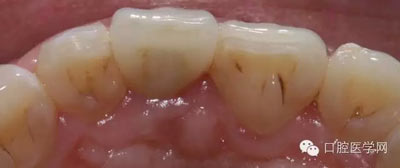

2、拆除烤瓷冠,牙體制備及11 3Mz350樹(shù)脂修復(fù)

3、由北京精藝義齒工作室高級(jí)技師靳曉輝老師制作的全瓷冠